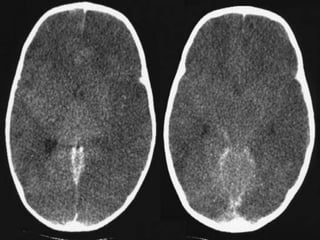

Causes of cerebral odema

• Infection.

• Mass lesion.

• Stroke.

• Metabolic causes.

• In true isolated cytotoxic oedema little change

is evident on CT as a mere redistribution of

water from extracellular to intracellular

compartments does not result in attenuation

changes. The changes colloquially ascribed to

'cytotoxic oedema' are in fact mostly due

to ionic oedema, and are described separately.

This is why brain CT is often normal in patients

with an acute ischaemic stroke.

Cytotoxic

• grey-white matter differentiation is

maintained and the oedema involves mainly

white matter, extending in finger-like fashion

• secondary effects of vasogenic oedema are

similar to cytotoxic oedema, with effacement

of cerebral sulci, with or without midline shift

Vasogenic